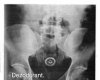

Ludzie to niesamowity gatunek. Potrafią tworzyć niesamowite rzeczy, ale jednocześnie potrafią być równie skretyniali co inteligentni. Mamy dla Was galerię niesamowitych szpitalnych zdjęć rentgenowskich na których uwieczniono człowieka i narzędzie zbrodni. Nigdy nie uwierzycie jakie przedmioty ludzie wkładają sobie w tyłek!